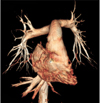

Fig. 1

Volume-rendered CT image with non-ECG-synchronized spiral scan shows excellent anatomic details of pulmonary arteries in 12-year-old girl with repaired coarctation of aorta.